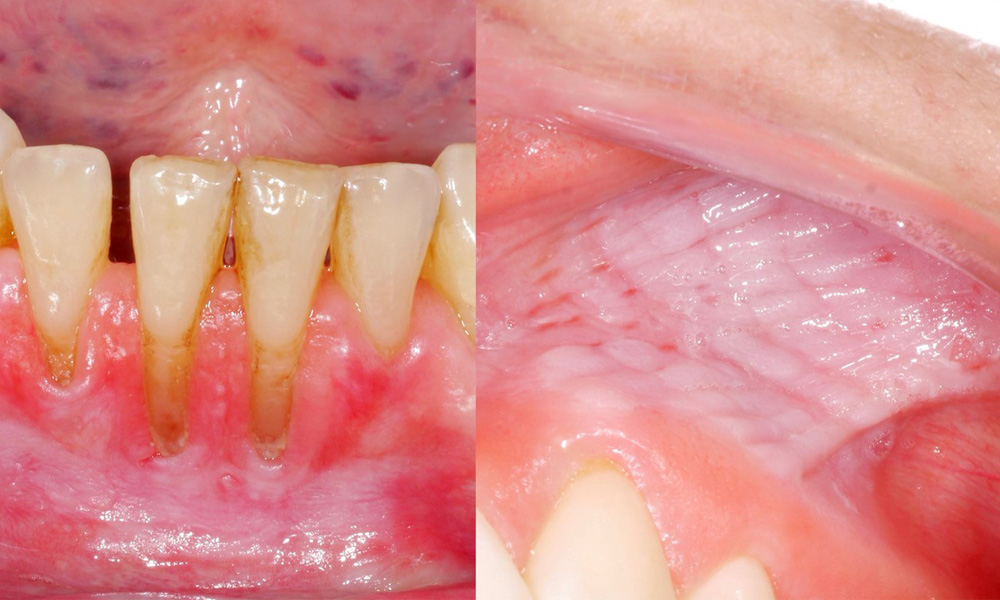

Клиничното изследване показа, че редовната консумация на снус може да има следните ефекти върху лигавицата на устната кухина:

• Приблизително 80% от изследваните лица, които са консумирали снус ежедневно, са показали лезии на лигавицата, предизвикани от него.

• За всяка допълнителна кутия снус, консумирана месечно, рискът от по-тежко увреждане на лигавицата се увеличава значително.

• Приблизително 20% от изследваните лица, които са консумирали снус ежедневно, са имали индуцирана гингивална рецесия.

• С всяка следваща година на употреба на снус рискът от индуцирана гингивална рецесия се увеличава значително.